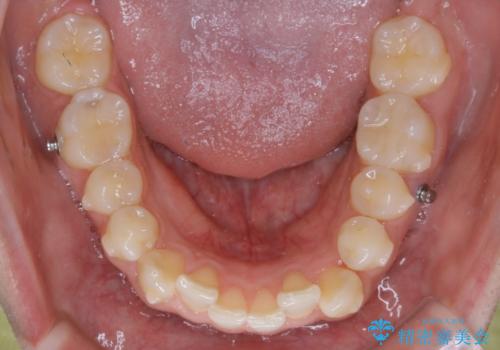

- マウスピース(インビザライン)

八重歯と噛み合わせえお治す必要がありましたが、抜歯を必要とするほどの状態ではなかったため非抜歯プランで治療を開始しました。

マウスピースとマイクロインプラントを組み合わせることで、抜歯をしなくても歯並びを治すためのスペースを作ることができます。奥歯から順に移動させていくので前歯に変化が出るまでには時間がかかりますが、その分健康な歯を抜歯することなく理想的な歯並びを手に入れることができます。